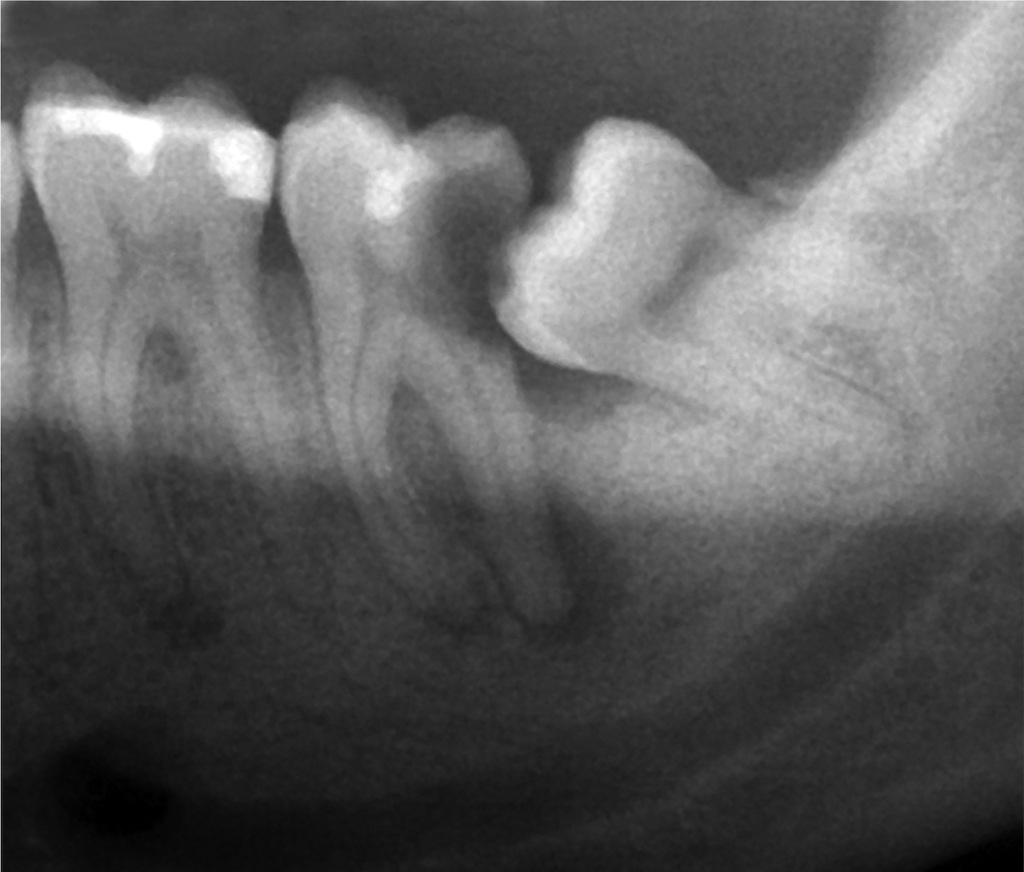

智慧齒 淨係發炎先有需要剝 一文了解智慧齒手術須知 Bowtie

口腔健康 無痛就毋須剝智慧齒 港大牙醫學院講解智慧齒的症狀與治療方法 Medical Inspire 醫 思維